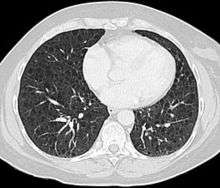

High-Resolution Computed Tomography: The high-resolution computed tomography (HRCT) chest scan is much more sensitive than the chest radiograph in detecting cystic parenchymal disease and is almost always abnormal at the time of diagnosis, even when the chest radiograph and pulmonary function assessments are normal.[19][21][22][100] The typical CT shows diffuse round, bilateral, thin-walled cysts of varying sizes ranging from 1 to 45 mm in diameter.[21][22] The numbers of cysts varies in LAM from a few to almost complete replacement of the normal lung tissue. The profusion of cysts tends to be milder in patients with TSC-LAM than S-LAM, perhaps explained in part by ascertainment of patients with TSC-LAM earlier in the disease process by screening.[25] Pleural effusions are seen on CT in 12% of patients with S-LAM and 6% of patients with TSC-LAM. Other CT features include linear densities (29%), hilar or mediastinal lymphadenopathy (9%), pneumothorax, lymphangiomyomata, and thoracic duct dilation.[21][22] Ground-glass opacities (12%) suggest the presence of interstitial edema due to lymphatic congestion. In patients with TSC, nodular densities on HRCT may represent multifocal micronodular pneumocyte hyperplasia (MMPH) made up of clusters of hyperplastic type II pneumocytes.[5][101][102] MMPH may be present in males or females with TSC in the presence or absence of LAM, but not in patients with S-LAM.[103] MMPH is not typically associated with physiologic or prognostic consequences, but one case of respiratory failure due to MMPH has been reported.[104] A review of diffuse cystic lung disease with specifics regarding LAM and the most common diseases in the differential diagnosis provides useful information to guide clinical decision-making.[105][106]